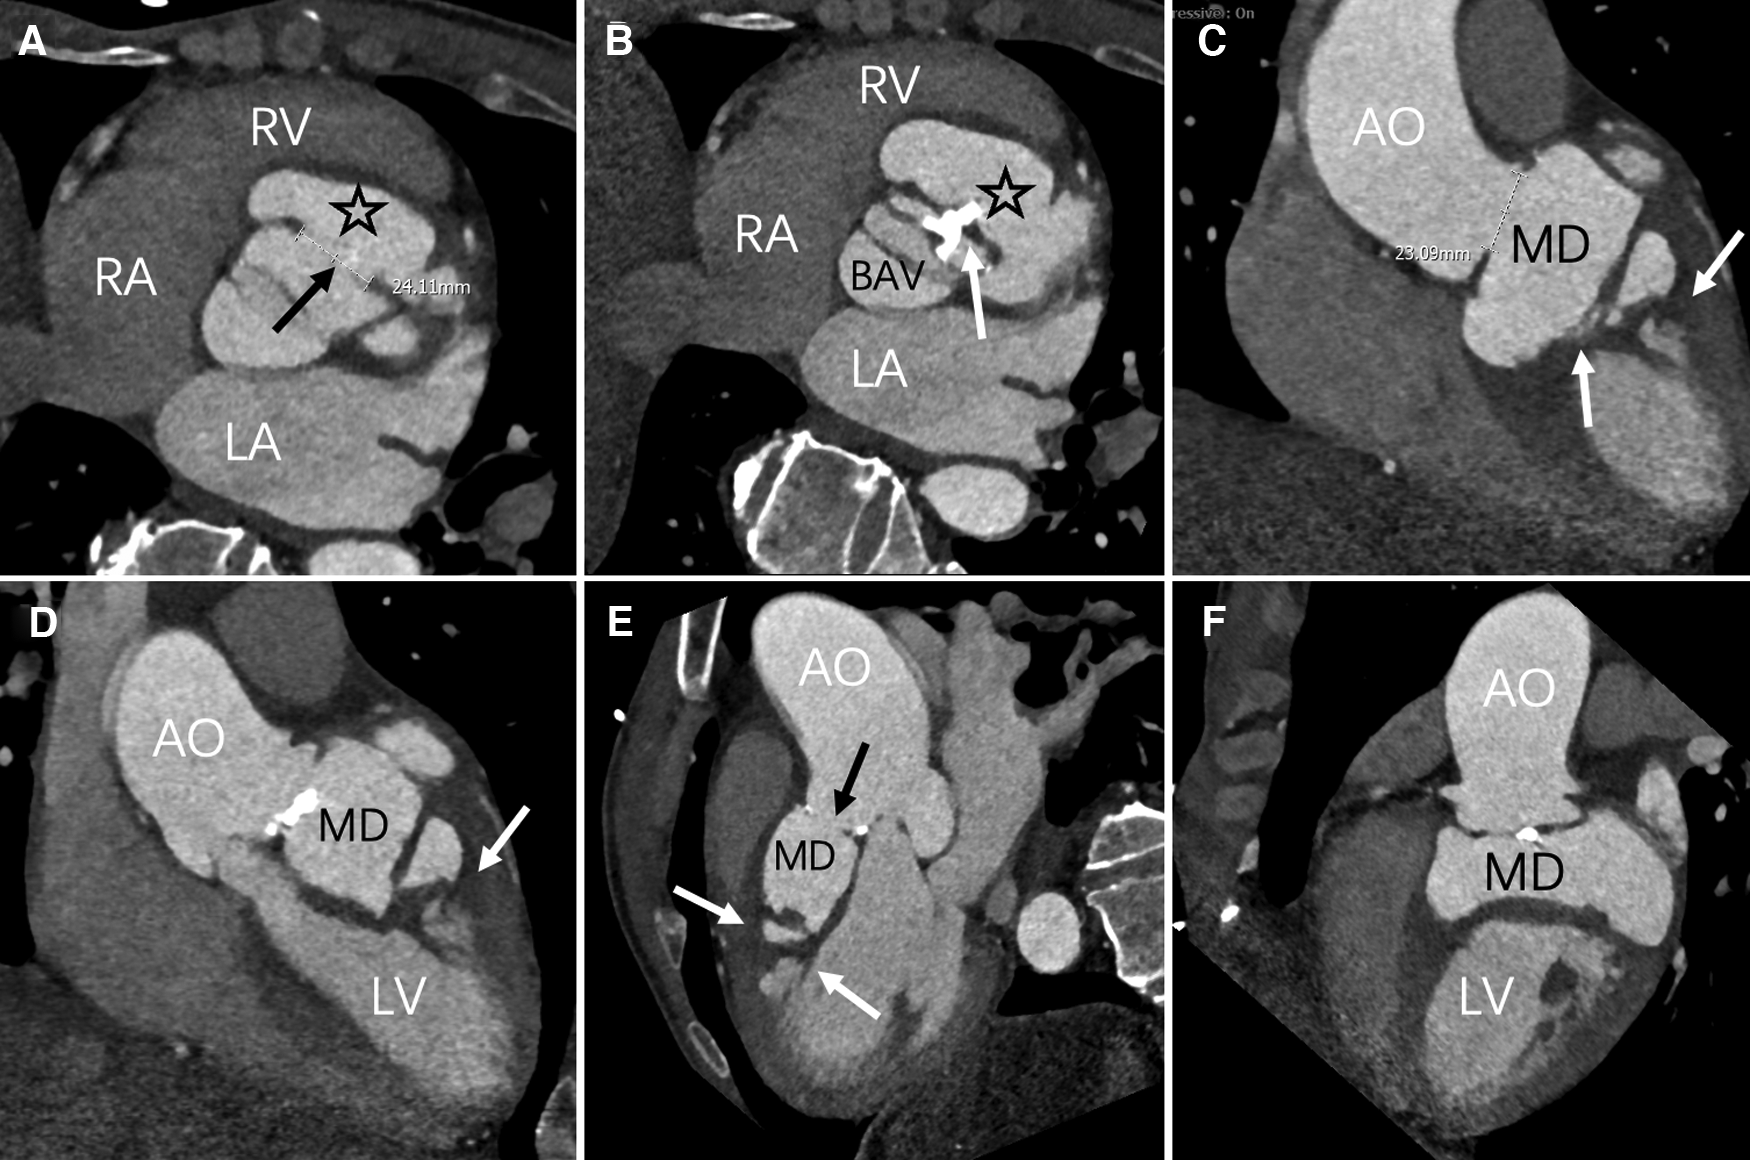

Figure 2

Axial position, contrast-enhanced CT imaging reveals the maximum aperture of the sinus of Valsalva aneurysm to be 2.4 cm (black arrow). The myocardial dissection originates from the fused left and right coronary sinuses (asterisk). A bicuspid aortic valve anomaly is evident, with valve leaflet thickening and calcification (white arrow) (C–F) multiPlanar Reconstruction (MPR) exhibits irregular MD, fusion of the left and right coronary sinuses (black arrow), and high-density opacities within the ventricular wall and interventricular septum (white arrow). LA, left atrium; LV, left ventricle; RA, right atrium; RV, right ventricle; AO, Aortic; MD, Myocardial dissection; BAV, bicuspid aortic valve.

A 60-year-old Chinese male presented with upper abdominal pain accompanied by dizziness and palpitations for 2 days. The patient's heart function was classified as NYHA functional class IV, and vital signs and blood biochemistry tests showed no critical indicators. Transthoracic echocardiography (TTE) revealed a myocardial dissection with a pouch-like protrusion into the right ventricle, interrupted wall echo in the septum and the basal segment of the left ventricular anterior wall, with an adherent hyperechoic structure within (Figure 1). A dual-source CT scan shows the diameter of the ascending aorta to be approximately 4.8 cm. There was a BAV and fusion of the left and right aortic sinuses, with an outward protrusion forming a cavity in the anterior aortic sinus. Myocardial dissection formation, likely due to rupture of the anterior aortic sinus, was suspected. The neck of the aneurysm had a diameter of approximately 1.4 cm, and the morphology of the aneurysm was irregular, with localized pushing on the left coronary artery (Figure 2).

CT imaging revealed a bicuspid valve in an L-R cusp fusion in this patient, with multiple calcifications on the leaflets. The merging of the left and right coronary sinuses forms a pouch-like structure. An irregularly shaped high-density shadow appears on the interventricular septum and the left ventricular wall, indicative of a myocardial dissection within the myocardium. CT provides high-resolution three-dimensional images, which offer a more intuitive basis for clinical decision-making and complement the results of echocardiography (12).